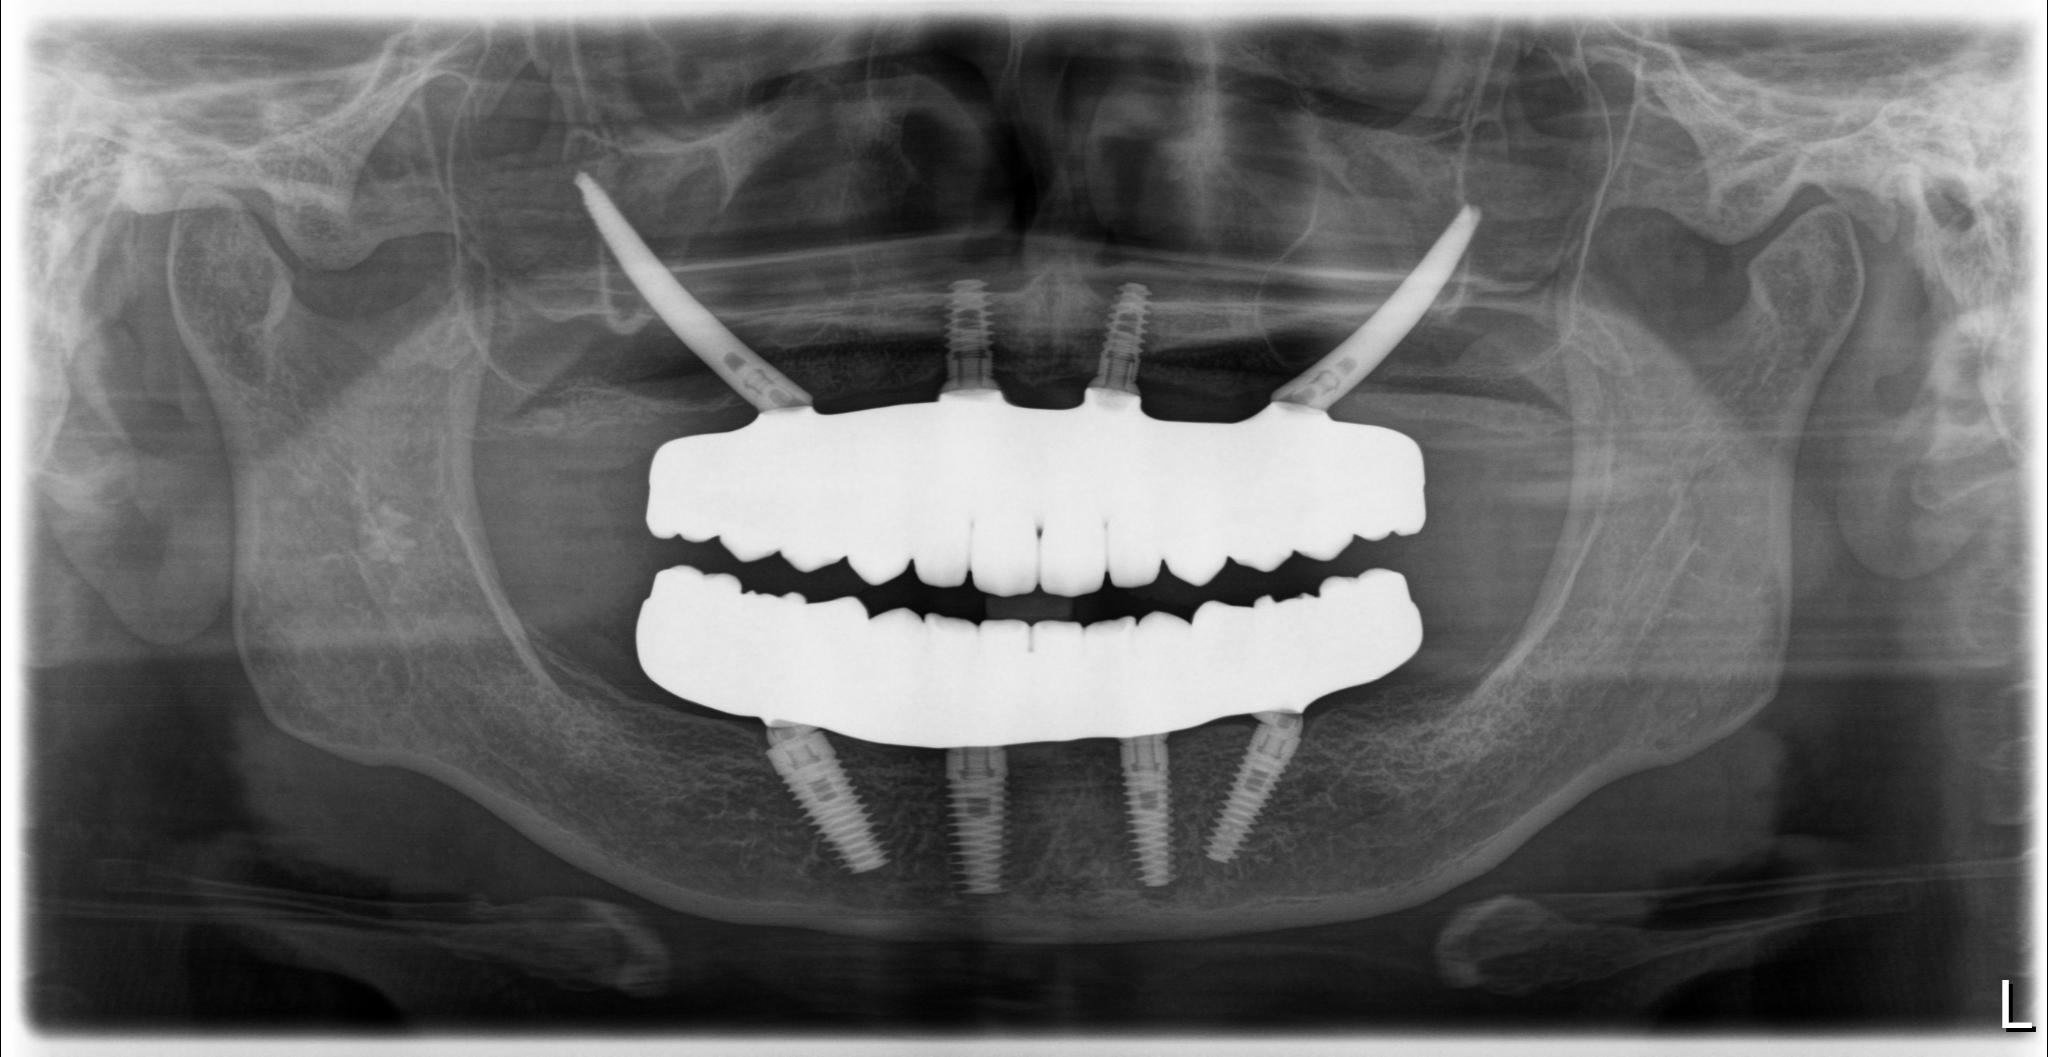

術後

内容 :上下顎オールオン4ザイゴマ2

費用 :5,552,800円

※モニター価格

期間 :半年

リスク:出血・腫れ・痺れ・痛み